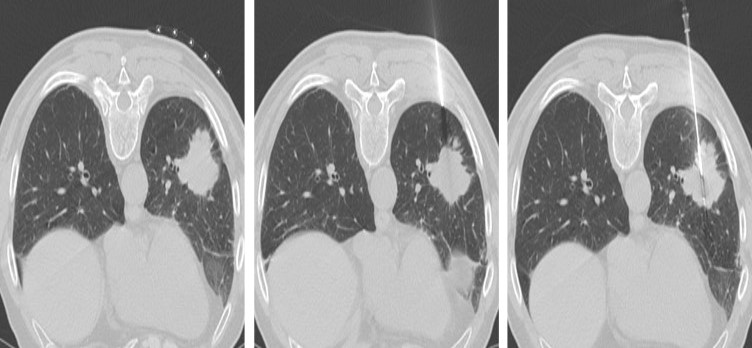

- Imagerie médicale : Le radiologue interventionnel va choisir la technique d’imagerie (échographie, scanner, radiologie) qui lui permettra de localiser avec précision la lésion cible et de pouvoir guider le plus précisément possible l’aiguille jusqu’à celle-ci . Pour les lésions profondes, le scanner est généralement utilisé avec un contrôle itératif de la progression de l’aiguille de biopsie. Pour les collection plus superficielles, l’échographie est souvent la technique de guidage la plus utilisée car elle permet de suivre en temps réel l’avancée de l’aiguille.

- Réalisation de la biopsie: Une aiguille fine servant à réaliser l’anesthésie locale est insérée sous guidage radiologique pour accéder à la la lésion cible. Tout le trajet d’accès est anesthésié. Une fois l’anesthésie locale réalisée, on met en place sous guidage radiologique une aiguille de plus large diamètre qui nous permettra de réaliser la biopsie. Au moment de la biopsie vous entendrez un petit bruit sec, « clac » , qui correspond à l’activation mécanique du système de prélèvement automatique.